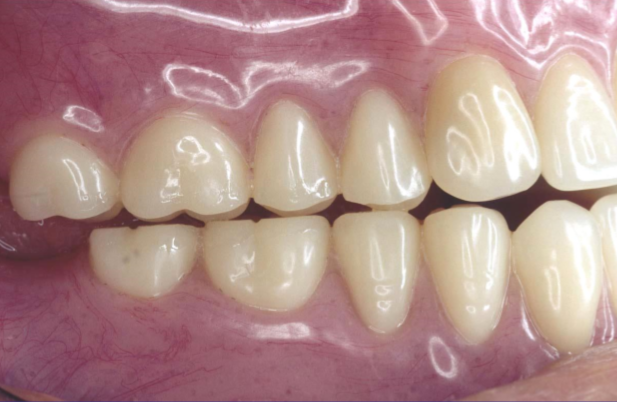

What are some advanced treatment options for edentulous patients?

What are some advantages of Overdentures?

What is the position of the posterior teeth in the Neutrocentric Concept (Monoplane)?

Over the residual ridge as far lingually as possible